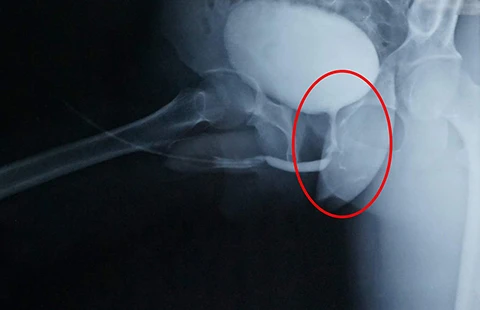

Sau đó BS tiến hành mổ đóng lỗ rò đường niệu cho bệnh nhân D. Đầu tiên, BS cho ống thông niệu quản đi từ miệng niệu đạo qua niệu đạo, qua lỗ rò và ra hậu môn. Sau đó BS rạch da vùng hội âm và bóc tách đến lỗ rò. Khi thấy ống thông niệu quản, BS kéo ống thông ra và cắt đôi. Lúc này có hai ống thông ngắn, kéo về hai phía cho thấy rất rõ lỗ rò ở niệu đạo và trực tràng.

“Tiếp theo, BS lần lượt cắt bỏ mô xơ và đóng các lỗ rò. Cuối cùng là cắt và xoay một vạt của thể xốp làm vách ngăn che giữa hai lỗ rò; sau một tuần, bệnh nhân tiểu thông qua đường tự nhiên, không còn rò rỉ ra hậu môn. Sau hai tuần, dương vật bệnh nhân cương cứng và xuất tinh ra ngả niệu đạo với chất lượng tinh trùng bình thường. Chúng tôi rất vui mừng khi D. hoàn toàn có khả năng làm cha” - BS Tâm cho biết.